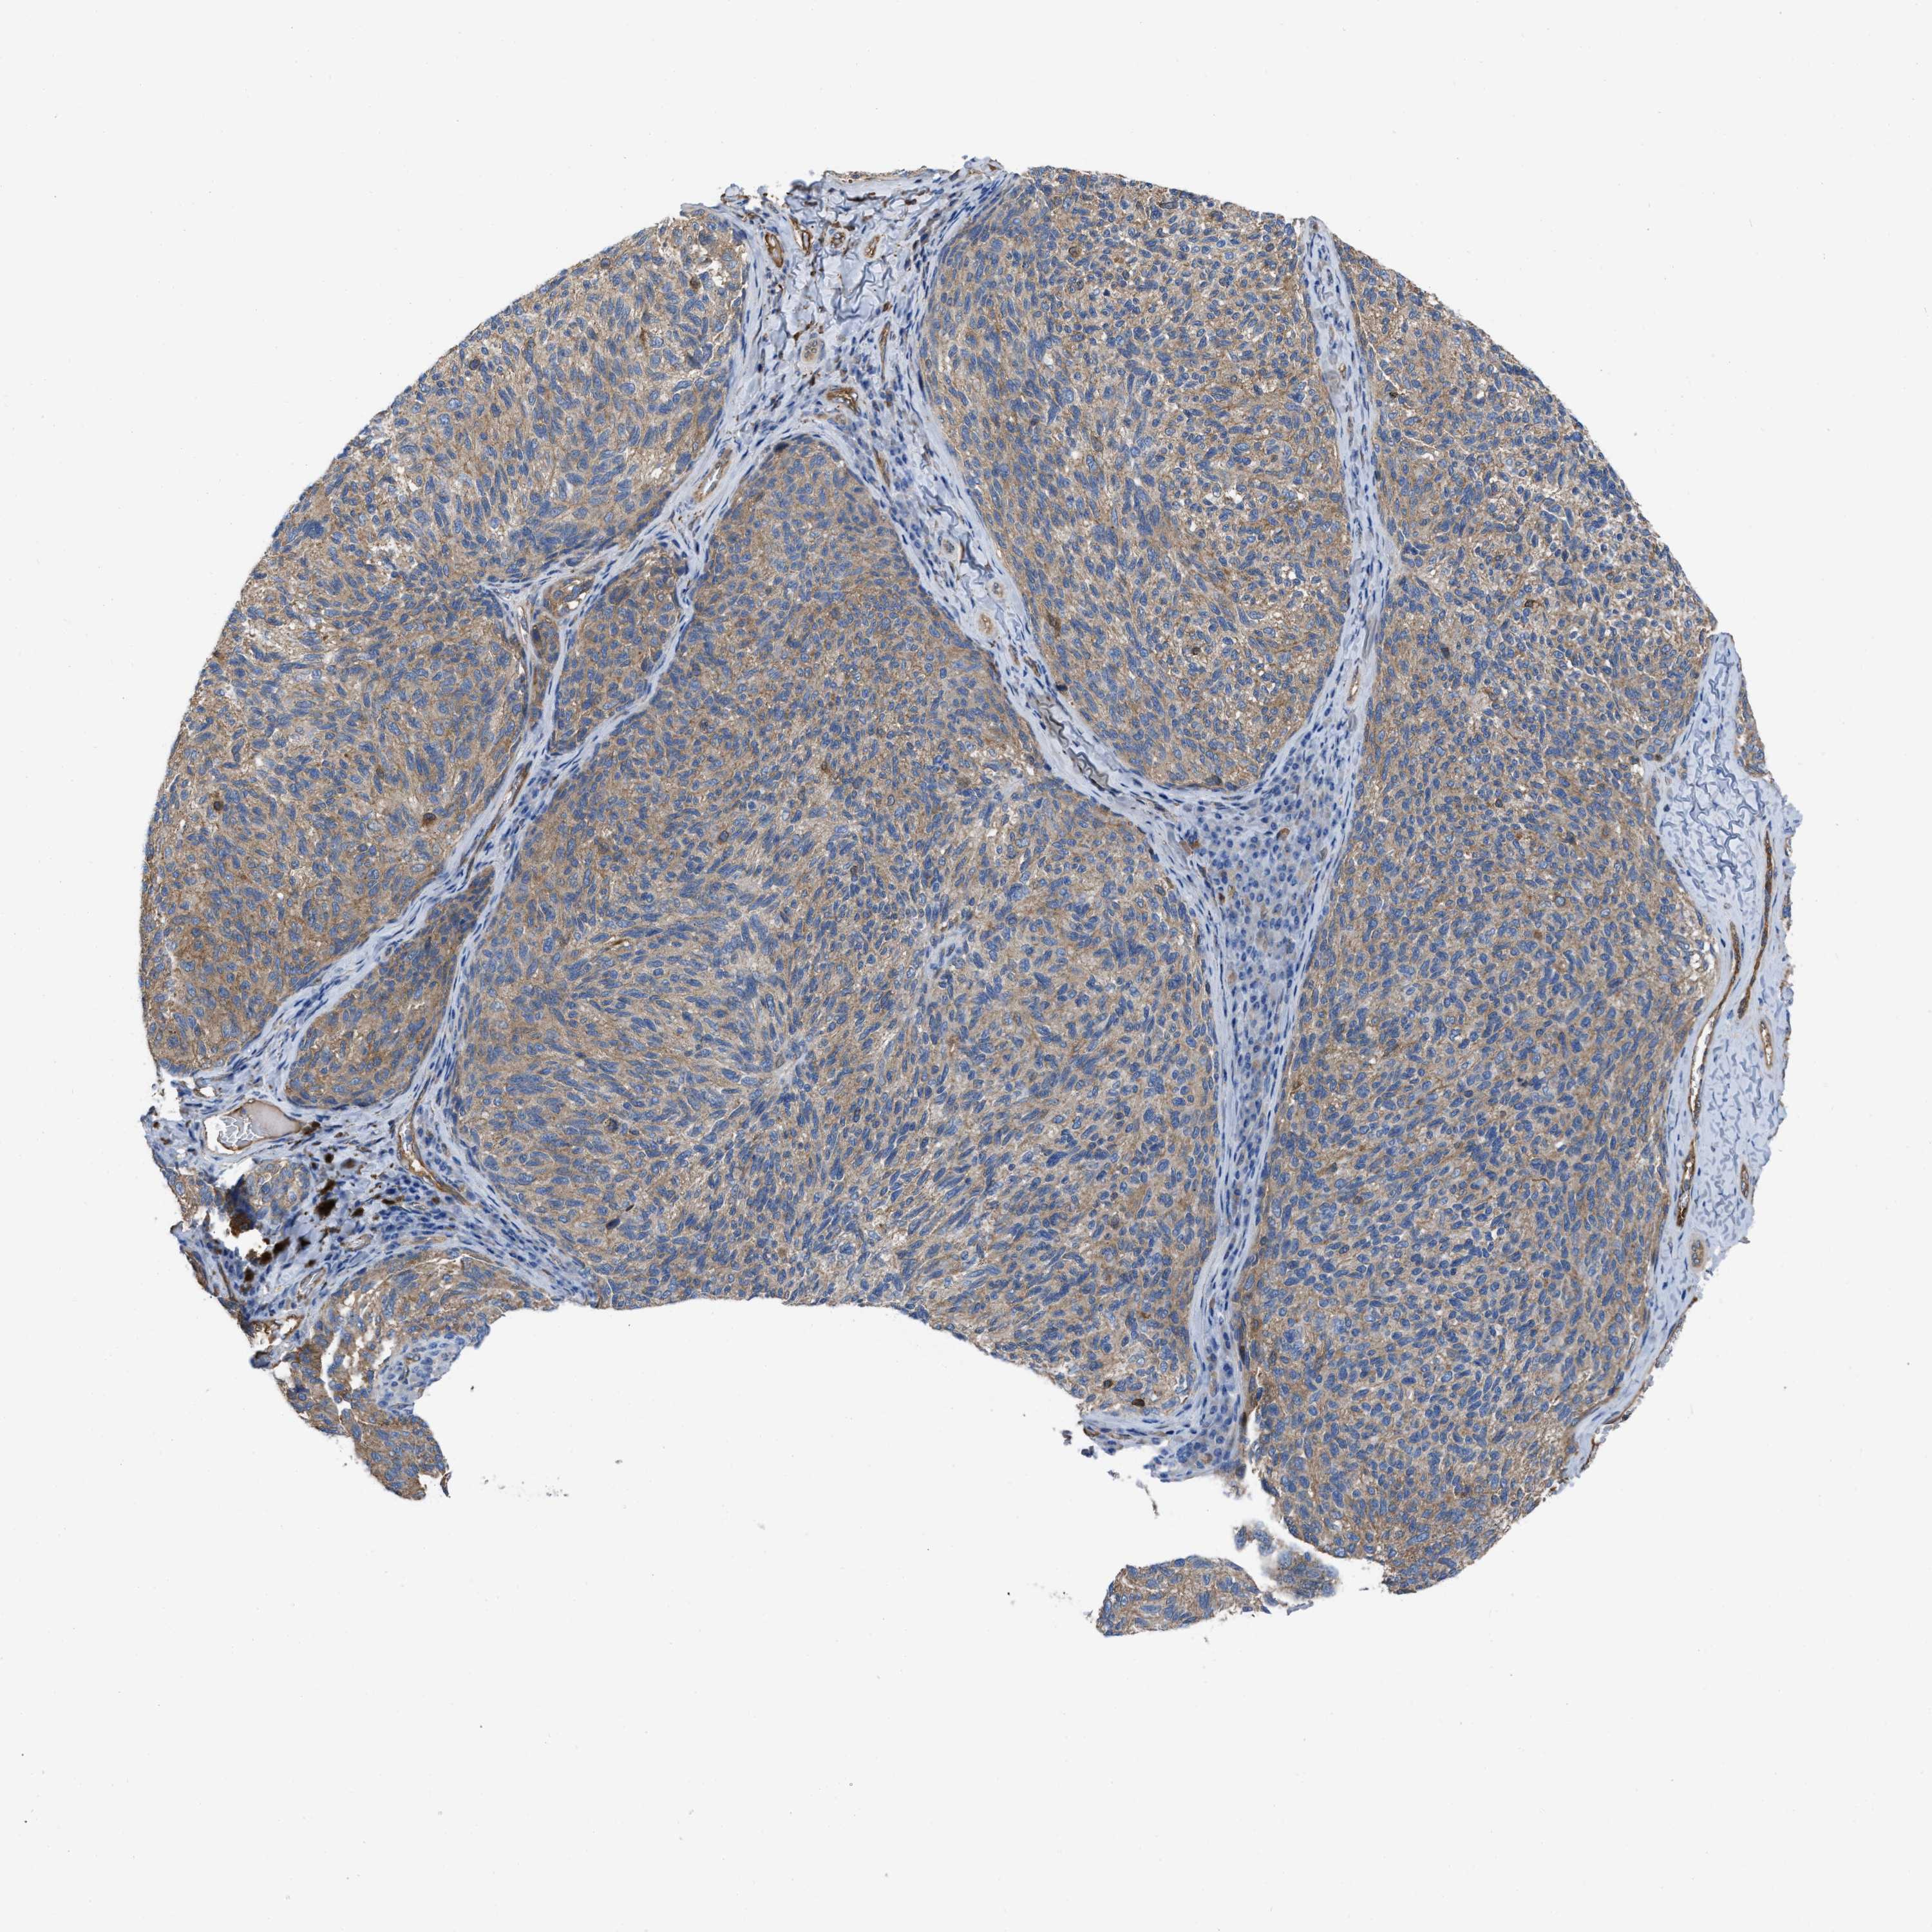

MELANOMA - Protein expressioni

A mouse-over function shows sample information and annotation data. Click on an image to view it in a full screen mode. Samples can be filtered based on level of antibody staining by selecting one or several of the following categories: high, medium, low and not detected. The assay and annotation is described here.

Note that samples used for immunohistochemistry by the Human Protein Atlas do not correspond to samples in the TCGA dataset.

Antibody stainingi

Antibody staining in the annotated cell types in the current human tissue is reported as not detected, low, medium, or high, based on conventional immunohistochemistry profiling in selected tissues. This score is based on the combination of the staining intensity and fraction of stained cells.

Each image is clickable and will lead to virtual microscopy that enables deeper exploration of all samples and also displays staining intensity scores, fraction scores and subcellular localization as well as patient and tissue information for each sample.

Antibody HPA003747

Antibody HPA019769

Staining

High

Medium

Low

Not detected

Intensity

Strong

Moderate

Weak

Negative

Quantity

>75%

75%-25%

<25%

None

Location

Nuclear

Cytoplasmic/membranous

Cytoplasmic/membranous,nuclear

Malignant melanoma, NOS

Malignant melanoma, Metastatic site